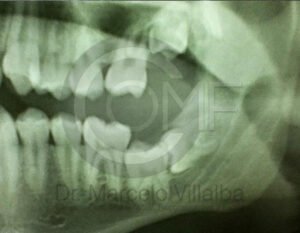

Antes de la extracción se realiza una valoración clínica y estudios de imagen, como radiografías panorámicas o tomografías, para conocer la posición del tercer molar, su relación con los nervios y planificar un procedimiento seguro y adecuado para cada paciente.

No es recomendable. Antes de extraer terceros molares es necesario realizar una valoración clínica y estudios de imagen para conocer la posición del diente, su relación con los nervios y el tipo de procedimiento más seguro para cada paciente.